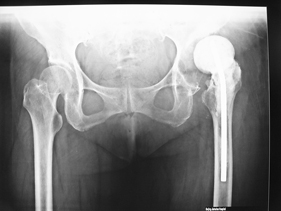

rivision total hip replacement for dislocation and severe bone defect

(pre-op) rivision total hip replacement for dislocation and severe bone defect

anterior-posterior view of bilateral hips